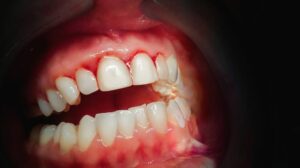

4. Gum Disease (Periodontal Issues)

Gum disease affects the tissues and bone that support your teeth. As it progresses, it can cause instability, making chewing uncomfortable or painful.

When gums and supporting bone weaken, teeth become unstable—making chewing painful.

Signs:

- Swollen or bleeding gums

- Bad breath

- Loose teeth

Treatment:

- Deep cleaning (scaling & root planing)

- Ongoing periodontal care